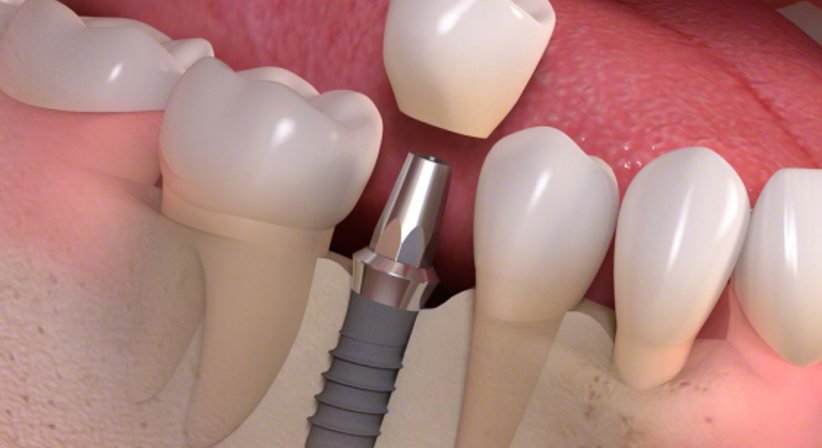

Zahnimplantate werden im Rahmen eines chirurgischen Eingriffes in den Kiefer eingesetzt. Zuvor erfolgt eine genaue und detaillierte Planung.

Nach einer Einheilzeit kann das Implantat mit einem Zahnersatz versorgt werden. In der Zwischenzeit kann ein Provisorium getragen werden.

Schöne und stabile Zähne dank moderner Zahnimplantat-Behandlung!